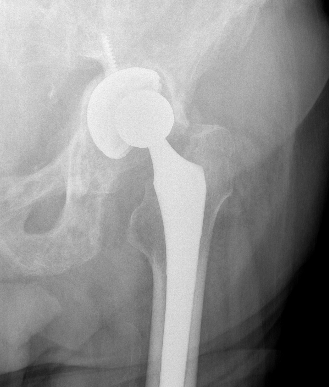

Cup Design

Stryker Trident Titanium and HA coated

Zimmer Trabecular Metal Tantalum Cup

Material

- titanium - similar modulus of elasticity to bone, most common

- tantalum - ? superior osteointegration, used often in revision

Porous coatings

- titanium / hydroxyapatite coating

- high coefficient of friction for initial rigid fixation

- pores allow bony ingrowth long term

Shape

- designed to engage in the outer periphery of acetabulum

- hemispherical / nonhemispherical / elliptical